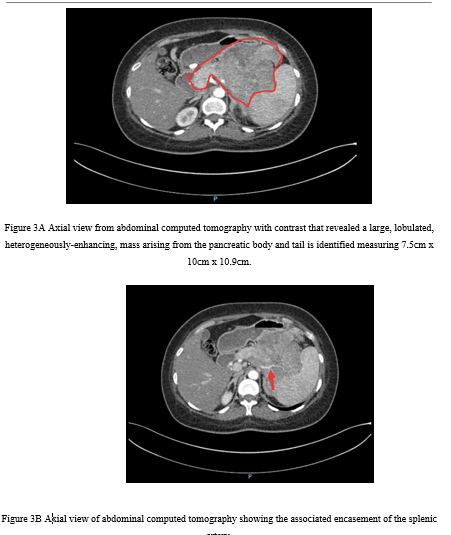

A low-dose 1-mg overnight dexamethasone suppression test produced an elevated serum cortisol of 991.03 nmol/L, showing unsuppressed morning cortisol, with an ACTH level of 577 pg/mL (reference, 7.2–63.3 pg/mL). Because of the markedly elevated ACTH, magnetic resonance imaging of the brain was performed to evaluate for a pituitary source but was negative (Figure 1). Cortisol levels remained elevated at >1750 nmol/L after the 8-mg high-dose dexamethasone suppression test, suggestive of an ectopic source.

Figure 1. Coronal view of a brain magnetic resonance imaging with contrast showing normal pituitary gland.